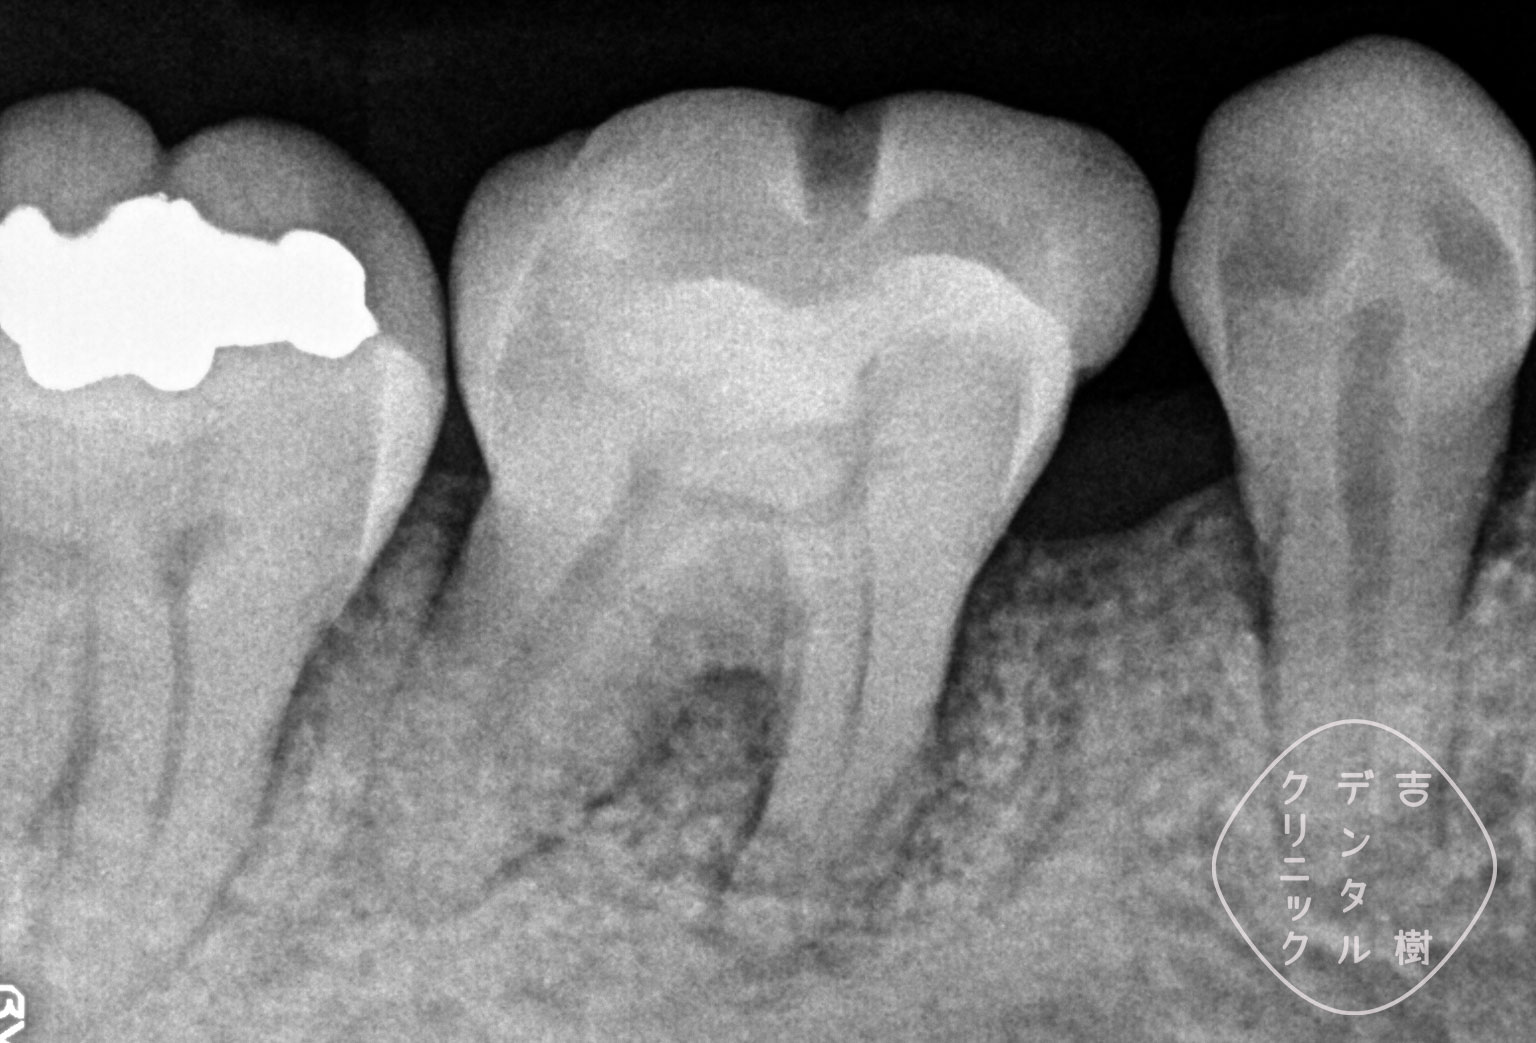

「歯周組織再生療法」により、失われた骨を再生した症例。

重度の歯周病で溶けてしまった骨を、「歯周組織再生療法」で再生した症例。